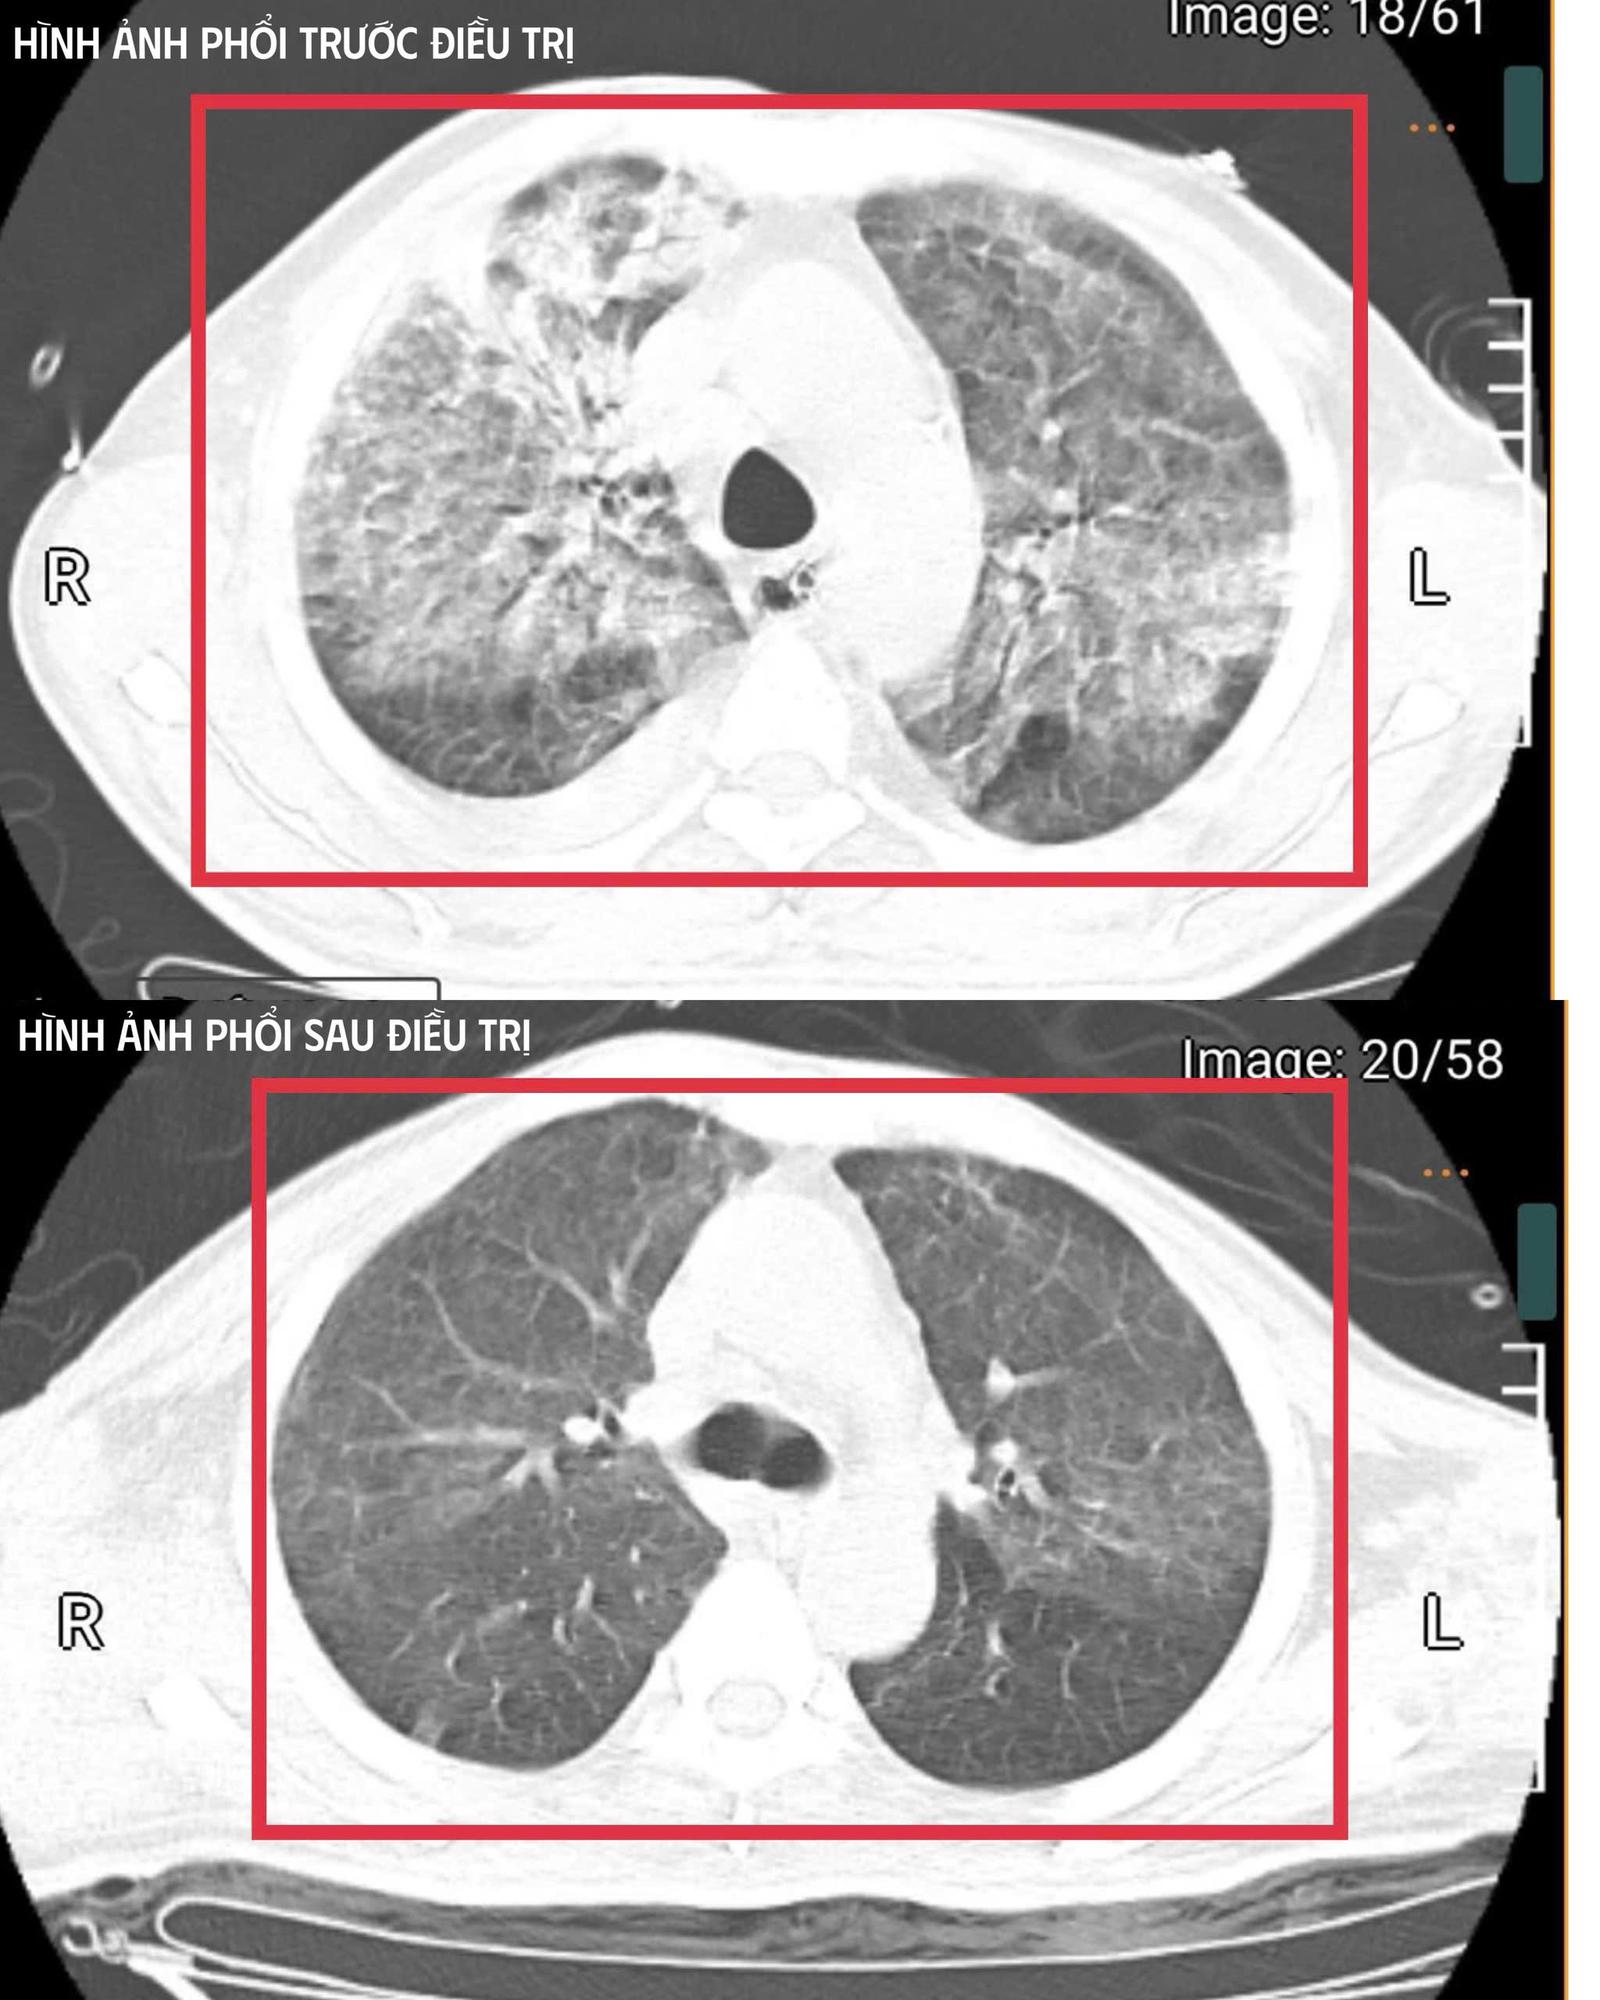

Hình ảnh chụp phổi của bệnh nhân mắc Whitmore. Ảnh: BVCC

Sau khoảng ba ngày, bệnh nhân bắt đầu cắt sốt, các chỉ số viêm giảm, thuốc vận mạch được hạ liều, chức năng gan thận cải thiện và tri giác dần hồi phục. Bệnh nhân được cai máy thở (qua mở khí quản), tập thở tự nhiên và phục hồi vận động.

Sau ba tuần điều trị, anh T. đã hồi phục hoàn toàn: tỉnh táo, tự thở khí phòng, huyết áp ổn định, cơ lực chi trên đạt 5/5 và chi dưới 4/5. Người bệnh được xuất viện và tiếp tục theo dõi ngoại trú.